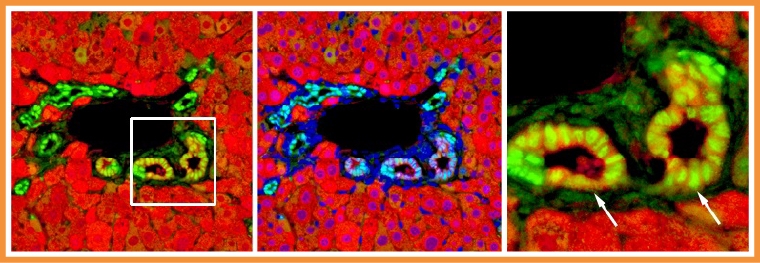

【NOW健康 楊芷晴/台北報導】肝臟是人體中少數具有再生修復能力的器官,最近陽明交大與哈佛大學聯手,發現了這項「自癒力」背後的基因,讓再生醫學帶來新的曙光。 ▲由肝細胞轉變而來的膽管上皮細胞。(圖/陽明交大生命科學系暨基因體科學研究所提供) 科學家發現抑制「HBO1」基因 有助肝細胞轉分化助再生修復 膽管的修復是肝臟多種自癒力表現之一。當膽管受損時,原本負責代謝功能的肝細胞竟能搖身一變為膽道上皮細胞,並且衝向前線修補受損的膽管。然而,這項轉變背後的分子機制長期未明。 ▲HBO1 是限制肝細胞命運轉換的表觀遺傳關卡。(圖/陽明交大生命科學系暨基因體科學研究所提供) 陽明交大與哈佛大學的科學家,發現了一個名為「HBO1」的基因扮演抑制肝細胞轉分化的「剎車」角色,讓肝細胞沒有辦法轉換為膽道上皮細胞。這意味著未來如有藥物能調控這個「剎車開關」,將有潛力激發肝細胞的可塑性,進一步應用於肝臟再生醫學或相關疾病的治療策略。 如能抑制HBO1採煞車的角色 就能讓肝細胞的染色質結構加快重塑 參與研究的陽明交大生命科學系暨基因體科學研究所助理教授袁維謙表示,HBO1會被轉錄輔助因子YAP引導到特定的基因組DNA位置,就像是被派去「踩煞車」一樣,藉著表觀遺傳機制,讓原本想啟動的基因無法順利開啟,從而抑制肝細胞的轉變。如能抑制HBO1採煞車的角色,就能讓肝細胞的染色質結構加快重塑,進而促進肝細胞轉分化為功能性膽道上皮細胞,加速膽管修復。 本研究成果發表於國際頂尖期刊《Cell Stem Cell》,研究團隊也將持續推進臨床前研究,期望將這項突破轉化為實際應用,為廣大肝病患者帶來新希望。 # 首圖來源/陽明交大生命科學系暨基因體科學研究所提供 更多NOW健康報導 ▸最新國人10大死因! 癌症連續43年蟬聯10大死因榜首 ▸健保永續藥師同行! 從給付制度、藥價政策到專業角色 NOW健康:FB │ IG │ Threads │ YT │ 官方LINE │ 醫級邦 │ 健康安妞 Podcast ❤溫馨提醒:歡迎轉傳「原始文章連結」分享,未經授權,請勿複製圖文轉貼本文。

膽管的修復是肝臟多種自癒力表現之一。當膽管受損時,原本負責代謝功能的肝細胞竟能搖身一變為膽道上皮細胞,並且衝向前線修補受損的膽管。然而,這項轉變背後的分子機制長期未明。

陽明交大與哈佛大學的科學家,發現了一個名為「HBO1」的基因扮演抑制肝細胞轉分化的「剎車」角色,讓肝細胞沒有辦法轉換為膽道上皮細胞。這意味著未來如有藥物能調控這個「剎車開關」,將有潛力激發肝細胞的可塑性,進一步應用於肝臟再生醫學或相關疾病的治療策略。

參與研究的陽明交大生命科學系暨基因體科學研究所助理教授袁維謙表示,HBO1會被轉錄輔助因子YAP引導到特定的基因組DNA位置,就像是被派去「踩煞車」一樣,藉著表觀遺傳機制,讓原本想啟動的基因無法順利開啟,從而抑制肝細胞的轉變。如能抑制HBO1採煞車的角色,就能讓肝細胞的染色質結構加快重塑,進而促進肝細胞轉分化為功能性膽道上皮細胞,加速膽管修復。